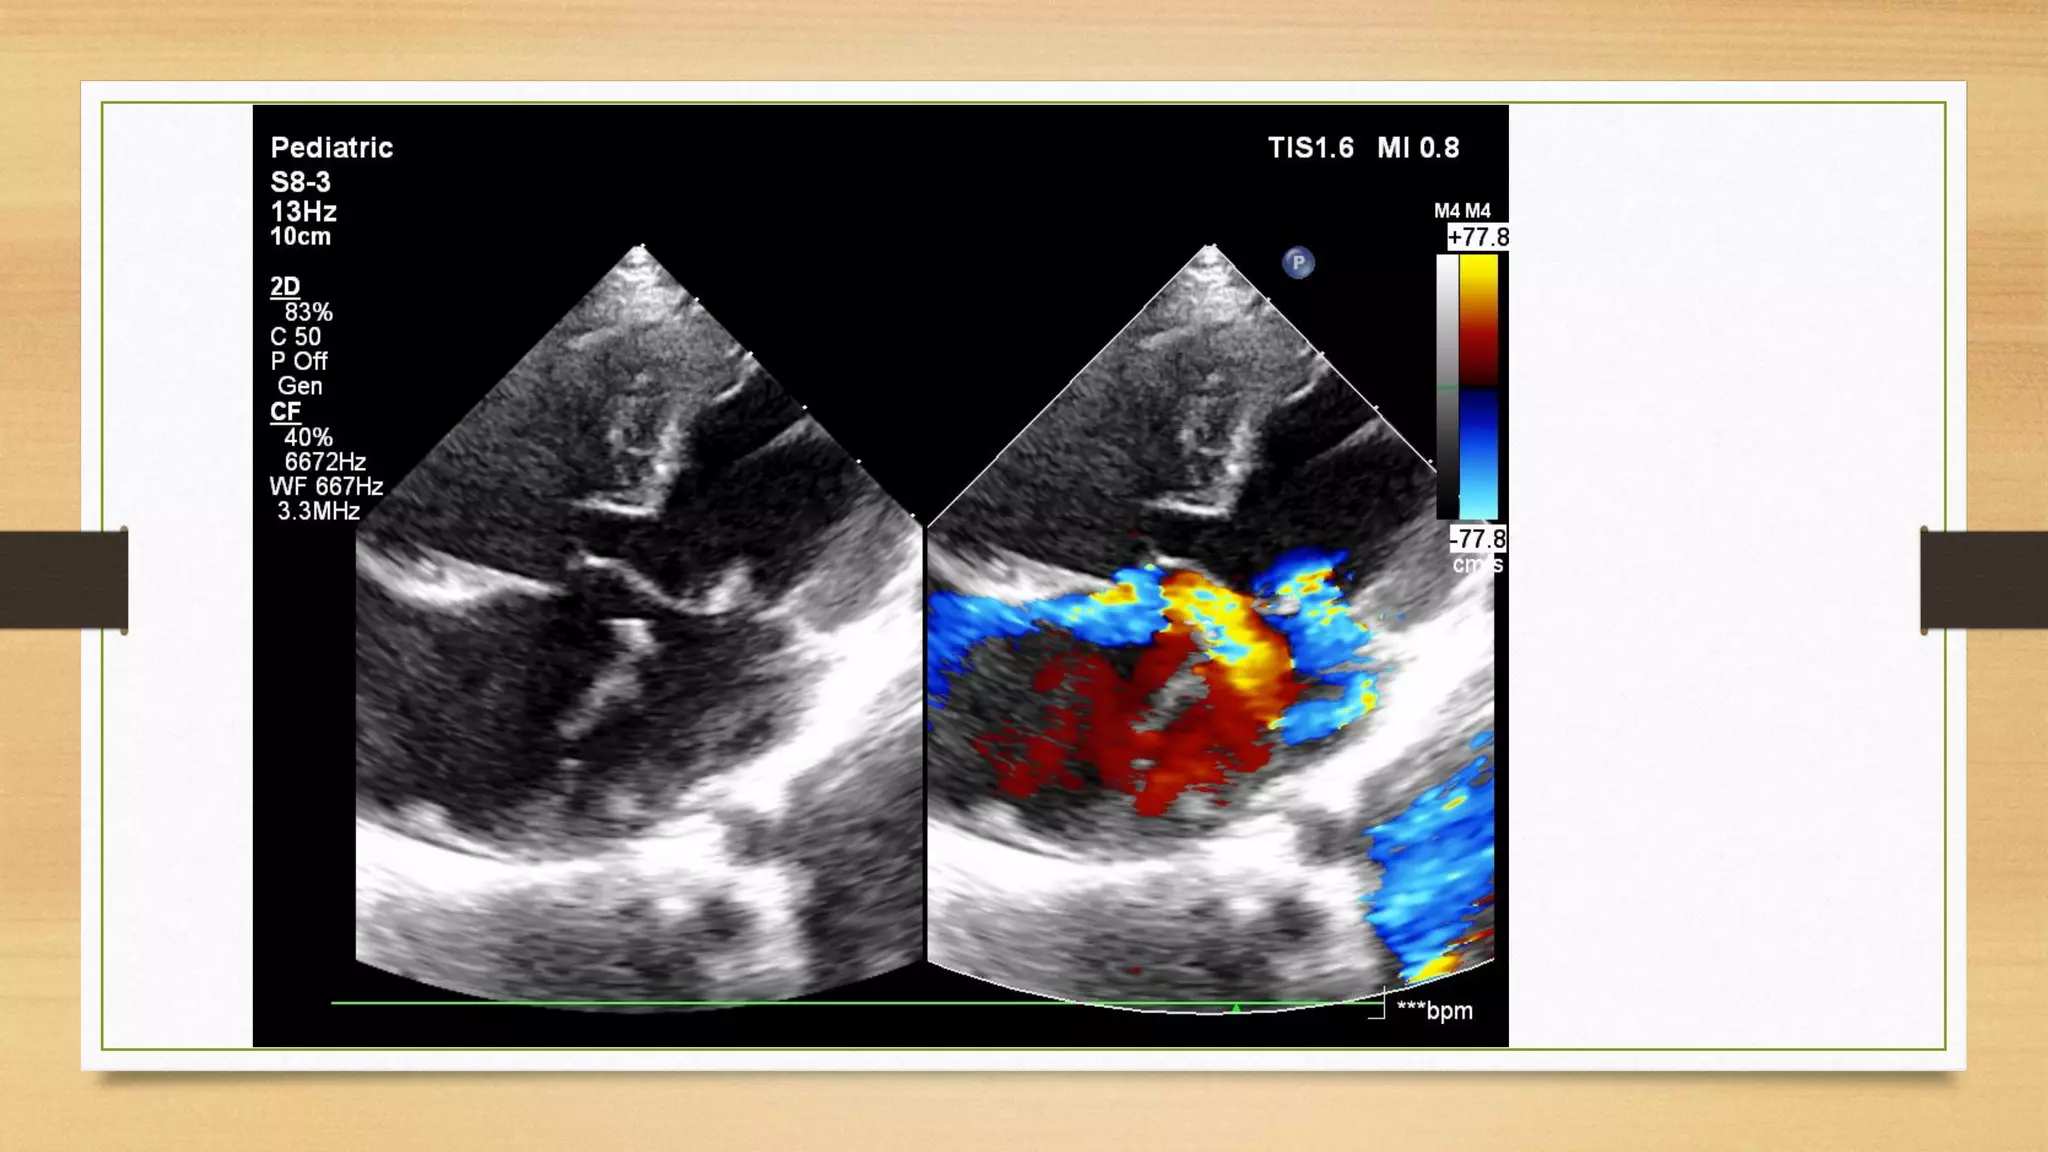

Echocardiography

It is the key tool for the diagnosis and assessment of size of atrial and

ventricular septal defects, size of the ventricles (balanced or unbalanced),

estimation of the pulmonary artery pressures, presence and severity of AV valve

regurgitation and for associated lesions such as left superior vena cava, left or

right ventricular outflow tract obstruction, and heterotaxy syndrome.

Primum Atrial Septal Defects

Echocardiography is the diagnostic modality of choice for delineation of all anatomic

features of AVSDs. The best transducer position to define the number and size of ASDs

is the subcostal view, as the plane of sound is perpendicular to the atrial septum. Both the

subcostal four-chamber and sagittal (bicaval) views are helpful in that regard. Color

Doppler delineates the shunt. The primum ASD in partial AVSD is typically large and easily

visualized in the subcostal, parasternal, and apical four-chamber projections. The TEE

four-chamber view readily demonstrates a primum ASD and the insertion of the tricuspid

and mitral valves onto the crest of the septum.